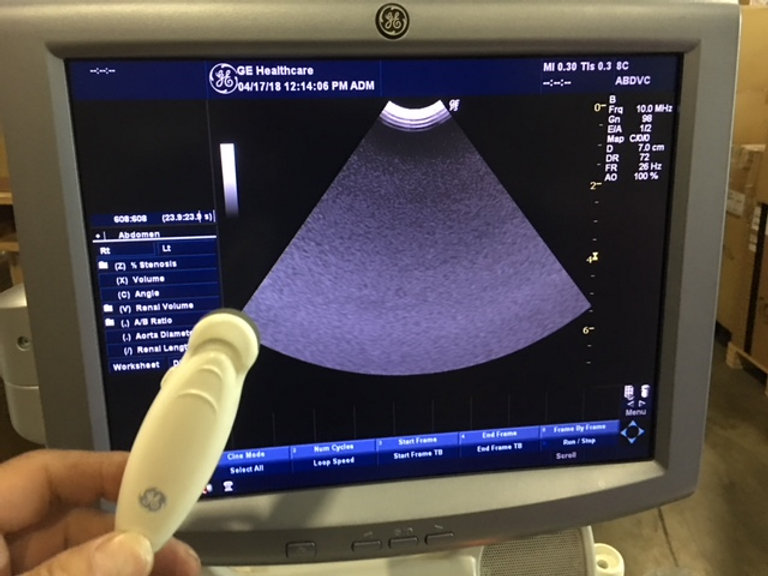

GE Logiq P5 d’occasion Lieu : Australie (U3075) Fabriqué : Oct 2013 Version du logiciel : R4.0.6 Options installées : Basic, Anatomical M, Cross Beam, SRI, Auto Sondes IMT : 5Sp, 8C, 11L